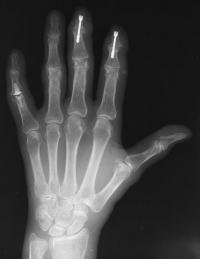

Second case.

This patient had previous experience with both DIP fusion and PIP arthroplasty.

Ring finger DIP joint of the opposite hand.

Xrays one year out.